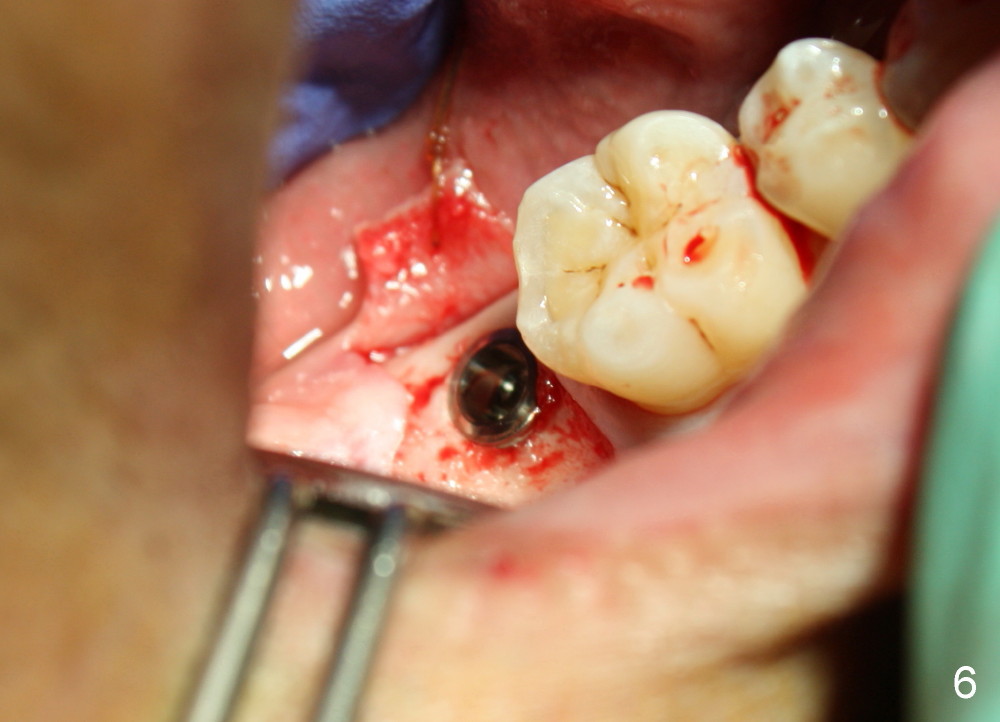

The implant is placed in the middle of the ridge buccolingually (Fig.6). A 6.2 x 3 (1) mm healing abutment is placed; the flaps tightly adapt to the abutment following suturing (Fig.7). The wound is then covered by perio dressing.